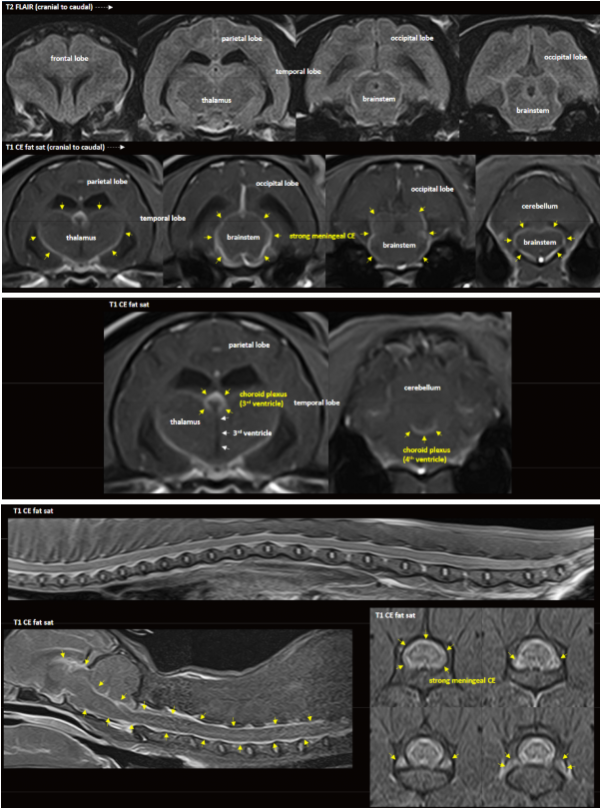

아이의 증상과 신경학적 소견을 바탕으로

뇌·흉요추 MRI 검사를 진행하였고,

영상 소견상 고양이 전염성 복막염이 강하게 의심되었습니다.

▪ MRI상 수막염 + 맥락총염 + 초기 뇌실막염/뇌실염 소견이 함께 관찰됨

▪ 환자의 어린 연령을 고려할 때 → FIP(고양이 전염성 복막염) 중 신경형 FIP 의심